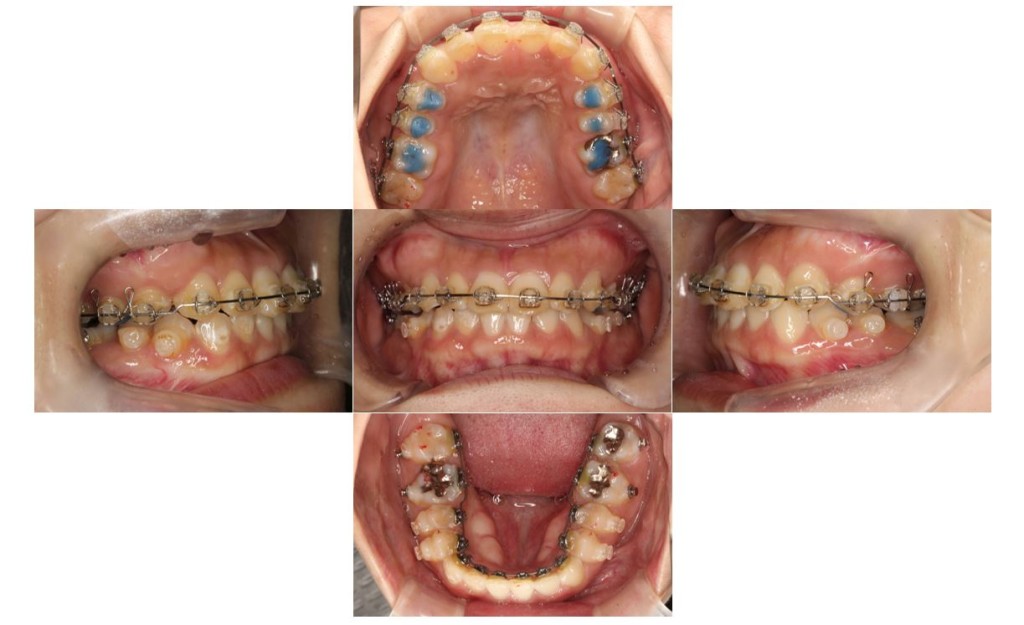

当院の症例

| 主訴 | ずっと気になっていた見た目、噛み合わせを含めて受け口を治したい。期間はかかってもいいので、外科手術をしないで歯列矯正だけで改善したい。 |

| 矯正の装置 | 裏側矯正から治療途中に表側矯正へ変更 |